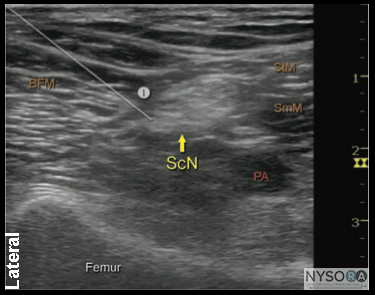

![]() Figure 7: Simulated needle path and the proper needle tip placement to block the sciatic nerve (ScN) through the lateral approach. BFM - Biceps femoris muscle, SmM - Semimembranosus muscle. StM - Semitendinosus muscle, PA- Popliteal artery. Technique With the patient in the proper position, the skin is disinfected and the transducer positioned to identify the sciatic nerve (Figure 5). If the nerve is not immediately apparent, tilting the transducer proximally or distally can help improve the contrast and bring the nerve "out" of the background (Figure 6). Alternatively, sliding the transducer slightly proximally or distally may improve the quality of the image and allow for better visualization. Once identified, a skin wheal is made on the lateral aspect of the thigh 2 to 3 cm above the lateral edge of the transducer. Then the needle is inserted in-plane in a horizontal orientation from the lateral aspect of the thigh and advanced toward the sciatic nerve (Figure 7). If nerve stimulation is used (0.5 mA, 0.1 msec), the contact of the needle tip with the sciatic nerve usually is associated with a motor response of the calf or foot. Once the needle tip is witnessed adjacent to the nerve, and after careful aspiration, 1 to 2 mL of local anesthetic is injected to confirm the proper injection site. Such injection should result in distribution of the local anesthetic within the epineural sheath, and often, separation of the TN and CPN. When injection of the local anesthetic does not appear to result in a spread around the sciatic nerve (Figure 8), additional needle repositions and injections may be necessary. When injecting into the epineurium, correct injection is recognized as local anesthetic spread proximally and distally to the site of the injection around both divisions of the nerve. This typically results in separation of TN and CPN during and after the injection.